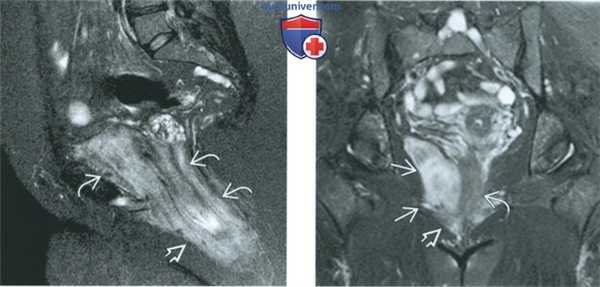

(Слева) При МРТ на ДВИ в аксиальной плоскости у той же пациентки с агрессивной ангиомиксомой отмечается выраженная диффузия в опухоли, располагающейся в левой половине вульвы.

(Справа) При МРТ на Т1-ВИ FS в корональной плоскости с контрастированием у пациентки с жалобами на боль в тазу определяется большая опухоль с инфильтрирующим ростом, характеризующаяся усилением сигнала при введении контрастного вещества. Опухоль прорастает мышцу, поднимающую задний проход, и переходит на вульву. Отмечается смещение мочевого пузыря опухолью. Исследование ткани хирургически удаленной опухоли показало, что она является агрессивной ангиомиксомой.

(Слева) При МРТ на Т2-ВИ FS в сагиттальной плоскости у той же пациентки с агрессивной ангиомиксомой опухоль гиперинтенсивна, имеет вытянутую форму и прорастает сквозь мышцу, поднимающую задний проход, в область вульвы (классический признак агрессивной ангиомиксомы).

(Справа) При МРТ на Т2-ВИ FS в корональной плоскости с контрастированием определяется дольчатая опухоль правой боковой стенки таза, характеризующаяся усилением сигнала при введении контрастного вещества. Опухоль оттесняет прямую кишку и распространяется на правую половину промежности. После хирургической операции диагноз агрессивной ангиомиксомы подтвердился.